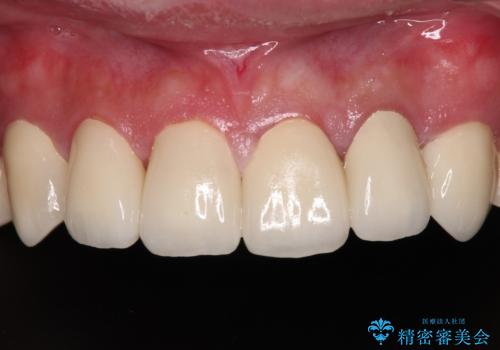

特に症状はなく、神経組織も健全な状態であったため、むし歯を全て取り切った後にフルジルコニアクラウンにて補綴することとしました。

銀歯などを使用する保険診療は、歯との境界の適合が悪く、むし歯の再発リスクが高いため、長期的な観点から使用は推奨されません。